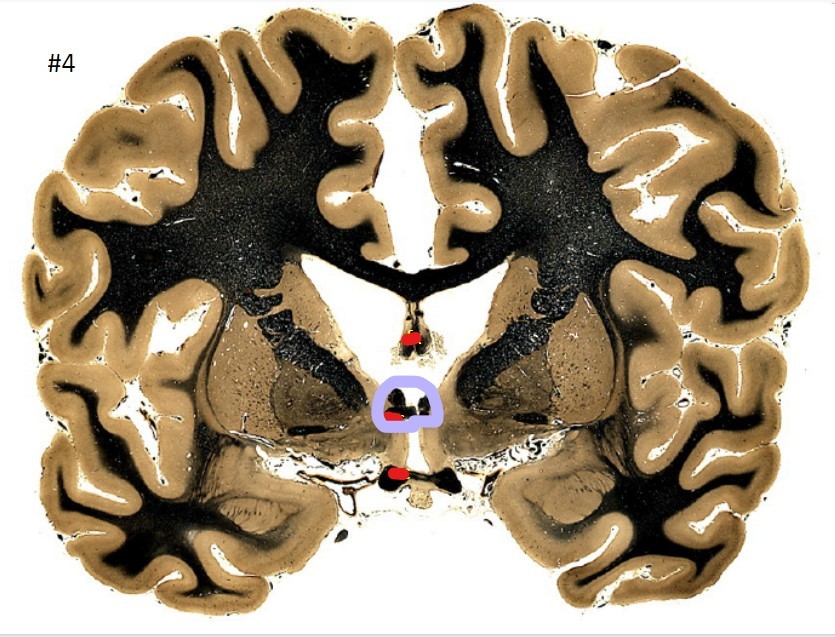

10

Q

what is the circled area (#4)?

A

the fornix

11

the anterior commissure

12

the optic chiasm

13

the putamen

14

the globus pallidus

15

the internal capsule

16

the caudate nucleus

17

the corpus striatum